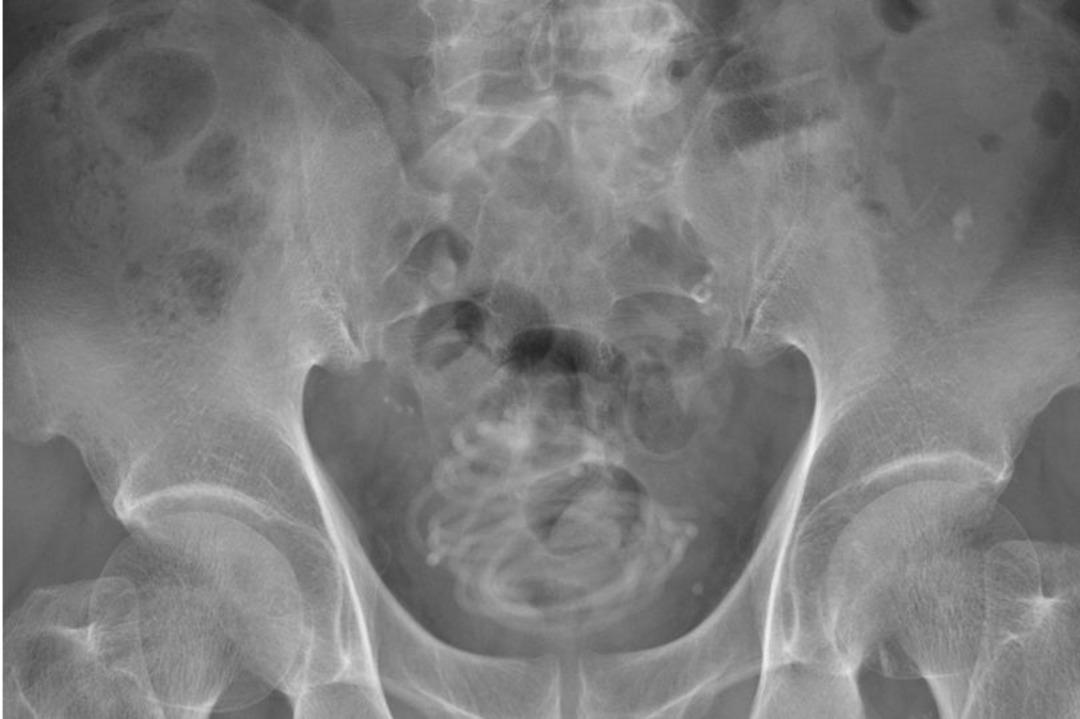

Tokyo’nun yaklaşık 100 kilometre kuzeyindeki bir hastanede adamın şikayeti üzerine ultrason dahil olmak üzere pek şok tarama yapıldı. Taramanın ortaya çıkardığı sonuçla kafaları karışan sağlık görevlileri daha sonra bir röntgen çektiler ve burada "tele benzer kıvrılmış bir yabancı cisim" buldular. Adam sonunda penisine bir atlama ipi soktuğunu itiraf etti.

İp mesanenin içinde düğümlendiği için sağlık görevlileri cerrahi işleme ihtiyaç duydu. Urology Case Reports'ta yayınlanan çalışmanın baş yazarı Profesör Toshiki Kijima, taramaların ve modellerin, dolaşıklık nedeniyle ipi penisten geri çekme şansının imkansız olduğunu kanıtladığını söyledi.